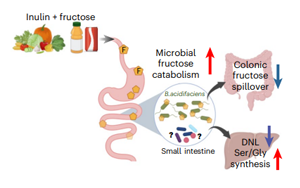

膳食纖維菊粉通過調(diào)控腸道菌群代謝果糖改善肝臟脂肪變性和胰島素抵抗的機制研究

為揭示菊粉緩解果糖毒性的深層機制,Sunhee Jung等研究人員在《Nature Metabolism》發(fā)表的研究采用了多組學整合分析策略。通過建立HFCS誘導的瘦型MASLD小鼠模型,結(jié)合穩(wěn)定同位素示蹤技術(13C-fructose和2H2O)動態(tài)監(jiān)測果糖代謝流向,采用宏基因組學解析菌群結(jié)構(gòu)變化,并運用轉(zhuǎn)錄組學和代謝組學系統(tǒng)評估肝臟代謝重編程。特別設計了延遲干預實驗組(CIF),驗證菊粉對已形成脂肪肝的逆轉(zhuǎn)效果。